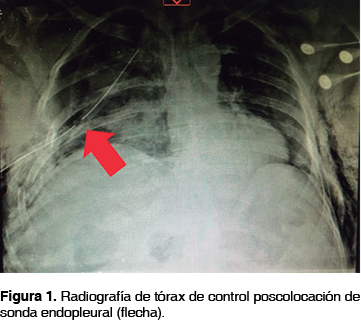

Se trata de un estudio retrospectivo, descriptivo y observacional que se llevó a cabo en el Hospital Central de la Cruz Roja Mexicana de la Ciudad de México, fueron revisados todos los expedientes de los pacientes de ambos sexos, masculino y femenino, y con un rango de edad de 18 a 45 años que ingresaron durante el período comprendido de febrero de 2007 a diciembre de 2013, con antecedente de traumatismo torácico contuso o penetrante y cuyas lesiones diagnosticadas de manera clínica o mediante estudios de gabinete: radiografía de tórax (figura 1), tomografía de tórax o eFAST (del inglés extended Focused Abdominal Sonography for Trauma o ultrasonido en trauma ampliado),14 ameritaron inserción de sonda endopleural para su resolución. Fueron excluidos los pacientes con necesidad de toracotomía de urgencia por hemotórax masivo, que no tuvieron indicación de colocación de sonda endopleural, que fueron trasladados a otro hospital antes de efectuar el retiro de la sonda y contar con evidencia radiográfica de ausencia de complicaciones o que ameritaron inserción de sonda endopleural como consecuencia de una toracotomía programada.